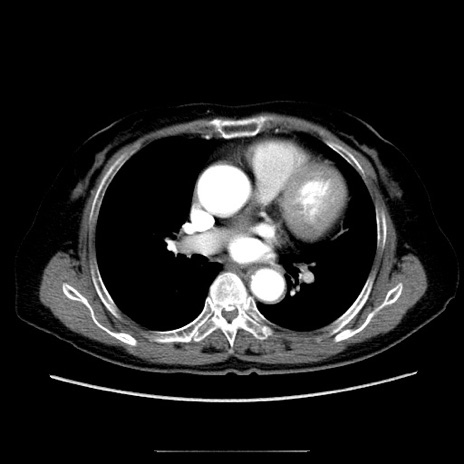

冠状断像

【症例】70歳代女性

【主訴】お腹が張る

【現病歴】1週間くらい前から腹部膨満の自覚あり。昨日夜から増悪したため、本日救急外来受診。

【身体所見】意識清明、BT 36.5℃、BP 165/106mmHg、HR 80bpm、SpO2 98%、腹部:膨満、軟、自発痛・圧痛なし、触診にて不快感あり、腸蠕動音:減弱

【データ】WBC 12600、CRP 1.04